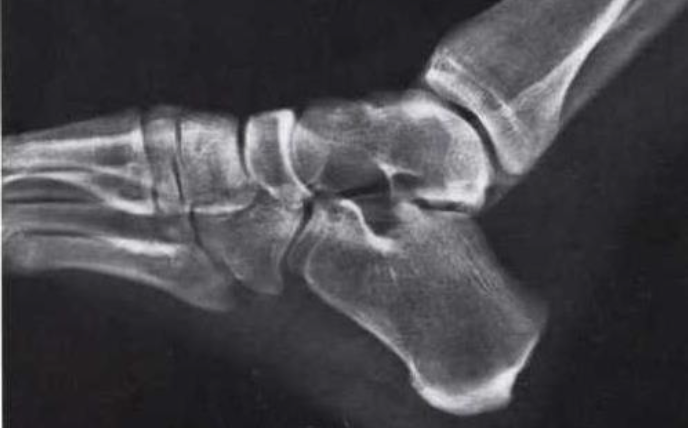

What is this view of the foot? what views are missing?

Oblique (medial)

MISSING:

Dorsal Plantar

Lateral